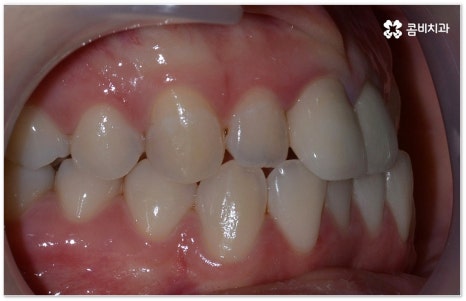

특히 업무적으로나 생활적으로 대인 관계가 활발하신 중장년 성인분들의 경우 치료 기간이 너무 오래 걸리지 않는지, 치아교정장치 가 너무 눈에 띄지는 않는지 궁금해 하시는 경우가 많이 있는데요. 말씀드렸던 것처럼 기술이 발달하면서 다양한 치아교정장치 가 나와있고 치아교정장치 자체는 결과에 크게 영향을 주지 않으므로 몇몇 케이스를 제외하면 환자분들께서 중요하게 생각하는 바 (심미성, 합리성 등) 를 반영할 수 있는 여지가 많이 있기 때문에 숙련된 의료진과 충분히 상담하셔서 각각의 장단점을 잘 살펴보시고 자신에게 꼭 맞는 장치를 고르시면 되니 크게 걱정하실 필요는 없을 거예요.

요즘 가장 많이 쓰이는 치아교정장치 인 클리피씨는 치아 색상의 세라믹 브라켓을 이용하기 때문에 심미성도 뛰어나고 자가결찰방식을 이용하여 보다 적은 힘으로 지속적이고 부드러운 치아 이동을 할 수 있도록 고안된 장치이므로 통증을 줄여줄 뿐 아니라 보통 2년 남짓 걸렸던 전체 교정 기간 역시 6개월 정도 감소시켜 줄 수 있습니다. 환자분들의 상황에 따라 내원 횟수 역시 줄일 수 있기 때문에 업무가 많이 바쁜 직장인분들의 경우에도 이용할 수 있다는 장점을 가지고 있어요.

이때 환자분들의 상황에 따라서 구조적인 원인이 크지 않고 교합이 심하게 어긋나지 않은 상태에서 치아의 각도만 살짝 앞으로 튀어나와 있거나 사이가 조금 벌어져 있는 등 부분 교정으로 치열을 가지런하게 바로잡을 수 있는 케이스도 있는데 이런 경우 6~8개월 정도의 보다 짧은 기간에 간편하게 치료를 끝낼 수 있으니 먼저 꼼꼼한 검진을 통해 자신이 부분 교정이 가능한지 여부를 알아보시면 좋을 거예요.

부정교합을 개선할 때 교합이 어긋난 정도가 심하고 구조적인 원인이 커서 부분 교정이 아닌 전체 교정이 필요한 케이스인 경우라고 해도 말씀드렸던 클리피씨 교정 장치 또는 보다 심미성을 강조한 치아교정장치 들의 도움을 통해 다른 사람과 얘기를 하거나 음식을 먹을 때 브라켓이 두드러지게 드러나는 부담을 줄일 수 있으니 설측교정, 콤비교정, 투명교정, 인비절라인 등에 대해서 한 번 알아보시고 각자에게 맞는 방법으로 교정 치료를 시작해 보시길 권유드리고 있어요.